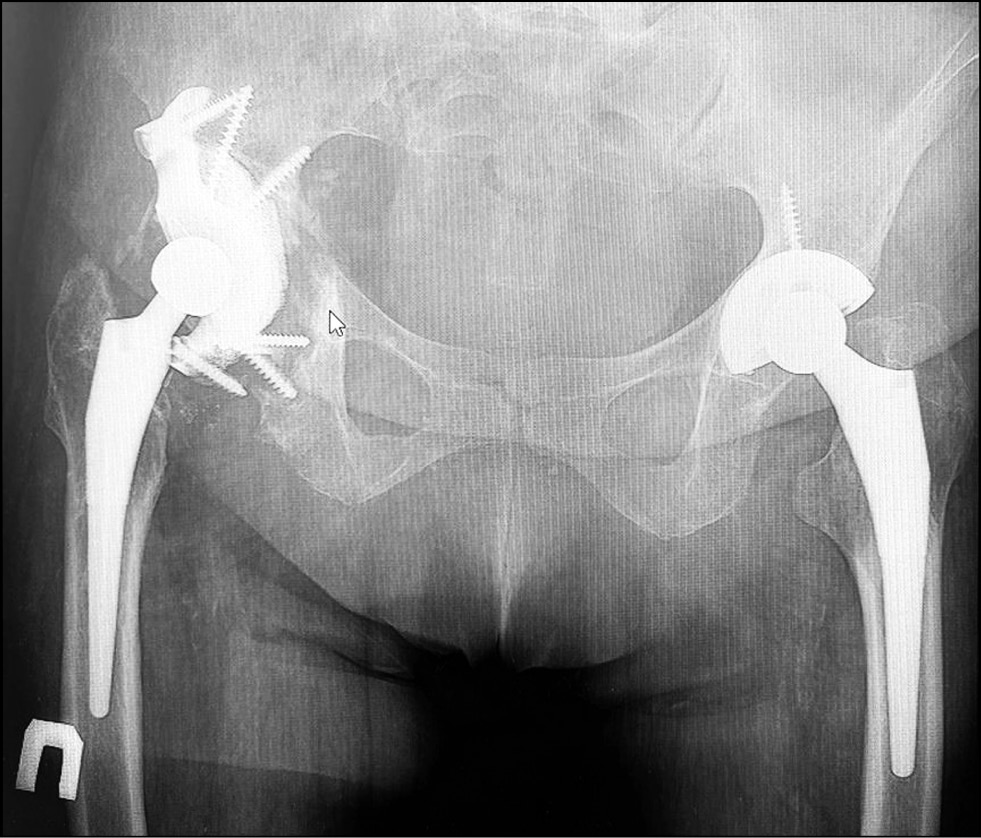

A 69-year-old patient underwent primary total hip replacement of the right hip joint with a Biomet endoprosthesis for right-sided coxarthrosis in 2010. In 2011, a similar operation using a Zimmer endoprosthesis was performed for left-sided coxarthrosis. In 2012, pain in the right hip joint region appeared and began to progress. In 2013, a revision hip replacement of the right hip joint was performed for acetabular component instability. Postoperatively, the patient noted repeated dislocations of the head of the right hip joint endoprosthesis with subsequent closed repositioning. In 2015, a revision hip replacement with a Burkh–Schneider antiprotrusion ring was performed for recurrent dislocations of the head of the right hip joint. Eighteen months after surgery, pain in the operated joint recurred. In November 2017, the patient was admitted to the endoprosthesis department of the N.N. Priorov National Medical Research Center of Traumatology and Orthopedics. The assessment of the right hip joint function according to the Harris hip scale (HHS) was 18 points, the severity of pain syndrome according to the visual analog scale (VAS) was 74 points (for a more accurate assessment, the scale was measured in millimeters), and the patient’s social adaptation according to the Western Ontario and McMaster Universities Osteoarthritis Index (WOMAC) scale was 92 points. Radiographs of the pelvic bones in a straight projection were obtained (Fig. 1).

Fig. 1. Preoperative radiograph of a 69-year-old patient: type IIIB acetabular defect according to W.G. Paprosky.